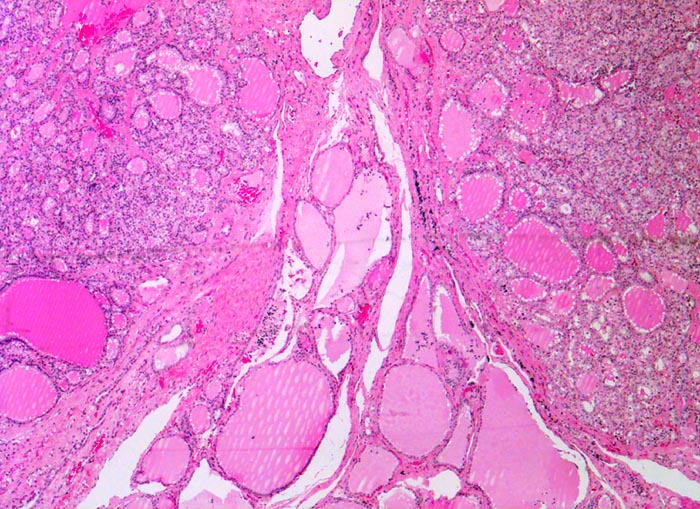

• Kompression des angrenzenden Schilddrüsenparenchyms. Dieses besteht aus grossen Follikeln mit kubischem oder abgeflachtem Epithel und reichlich kompaktem dunklem Kolloid in den Follikellumina.

• Zeichen gesteigerter hormoneller Aktivität im Adenom:

• Kleine Drüsenlumina.

• Teils mehrreihiges kubisches bis zylindrisches Epithel.

• Fehlendes oder nur spärliches helles Kolloid mit zahlreichen Resorptionsvakuolen.